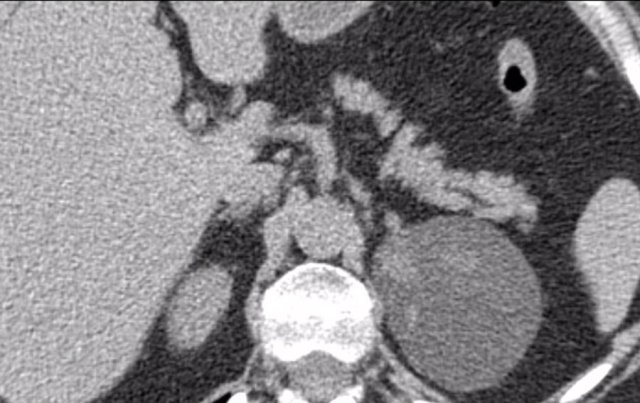

The axial venous phase CT on the left shows a large inhomogeneously enhancing right adrenal lesion with a small cyst, which could not be diagnosed as an adenoma with CT washout, making it an indeterminate lesion.

The plasma free metanephrines were elevated and the lesion was diagnosed as a pheochromocytoma.

MIBG SPECT for staging showed intense uptake in only the right adrenal gland.

PET-CT was also performed, which in contrast showed uptake only slightly higher than normal liver.

This is highly unusual for pheochromocytomas, which are usually very FDG-avid, even when they are benign.

If the primary tumor lacks FDG uptake, the sensitivity for finding metastases on an FDG PET-CT will be very low.